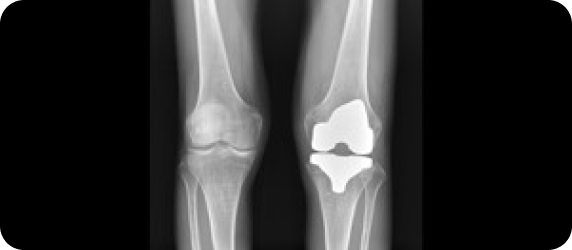

▲ 무릎 수술환자의 스캐노그램 엑스레이 검사